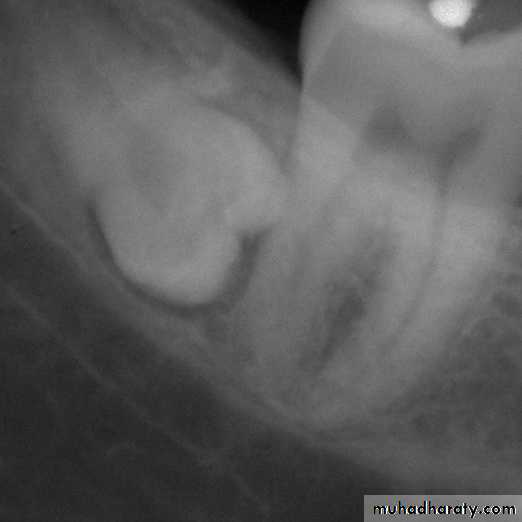

( A and B ) of the same patient taken 7 years apart reveal thickening of the lamina dura around the teeth.

A

B